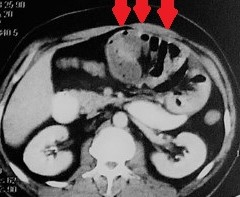

CT κοιλίας. Κόκκινο βέλος – Παγκρεατίτιδα – Περιπαγκρεατική συλλογή στον σπληνονεφρικό χώρο (Ευγενική παραχώρηση Dr. V. Penopoulos)